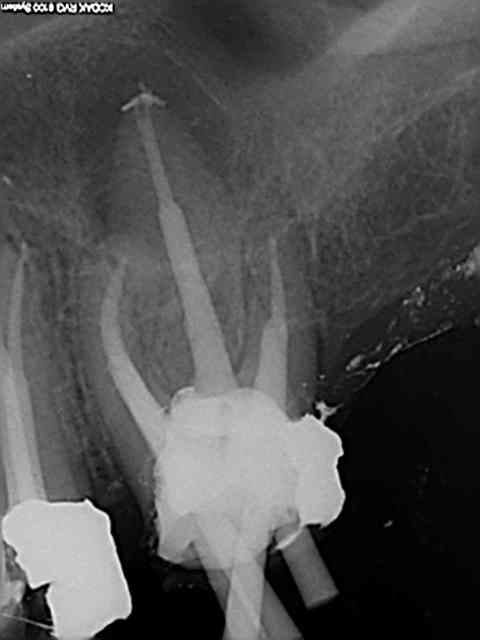

Et une de plus !

R19 vxiysf - Eugenol

R20 kboz6l - Eugenol

01 ukhwbq - Eugenol

C'est pas de la frime hein, mais ca fait plaisir d'avoir trouvé ENFIN une technique rapide et reproductible sans casse. (enfin presque il y a dans le tas un micro morceau de R25 pas loin de l'apex )